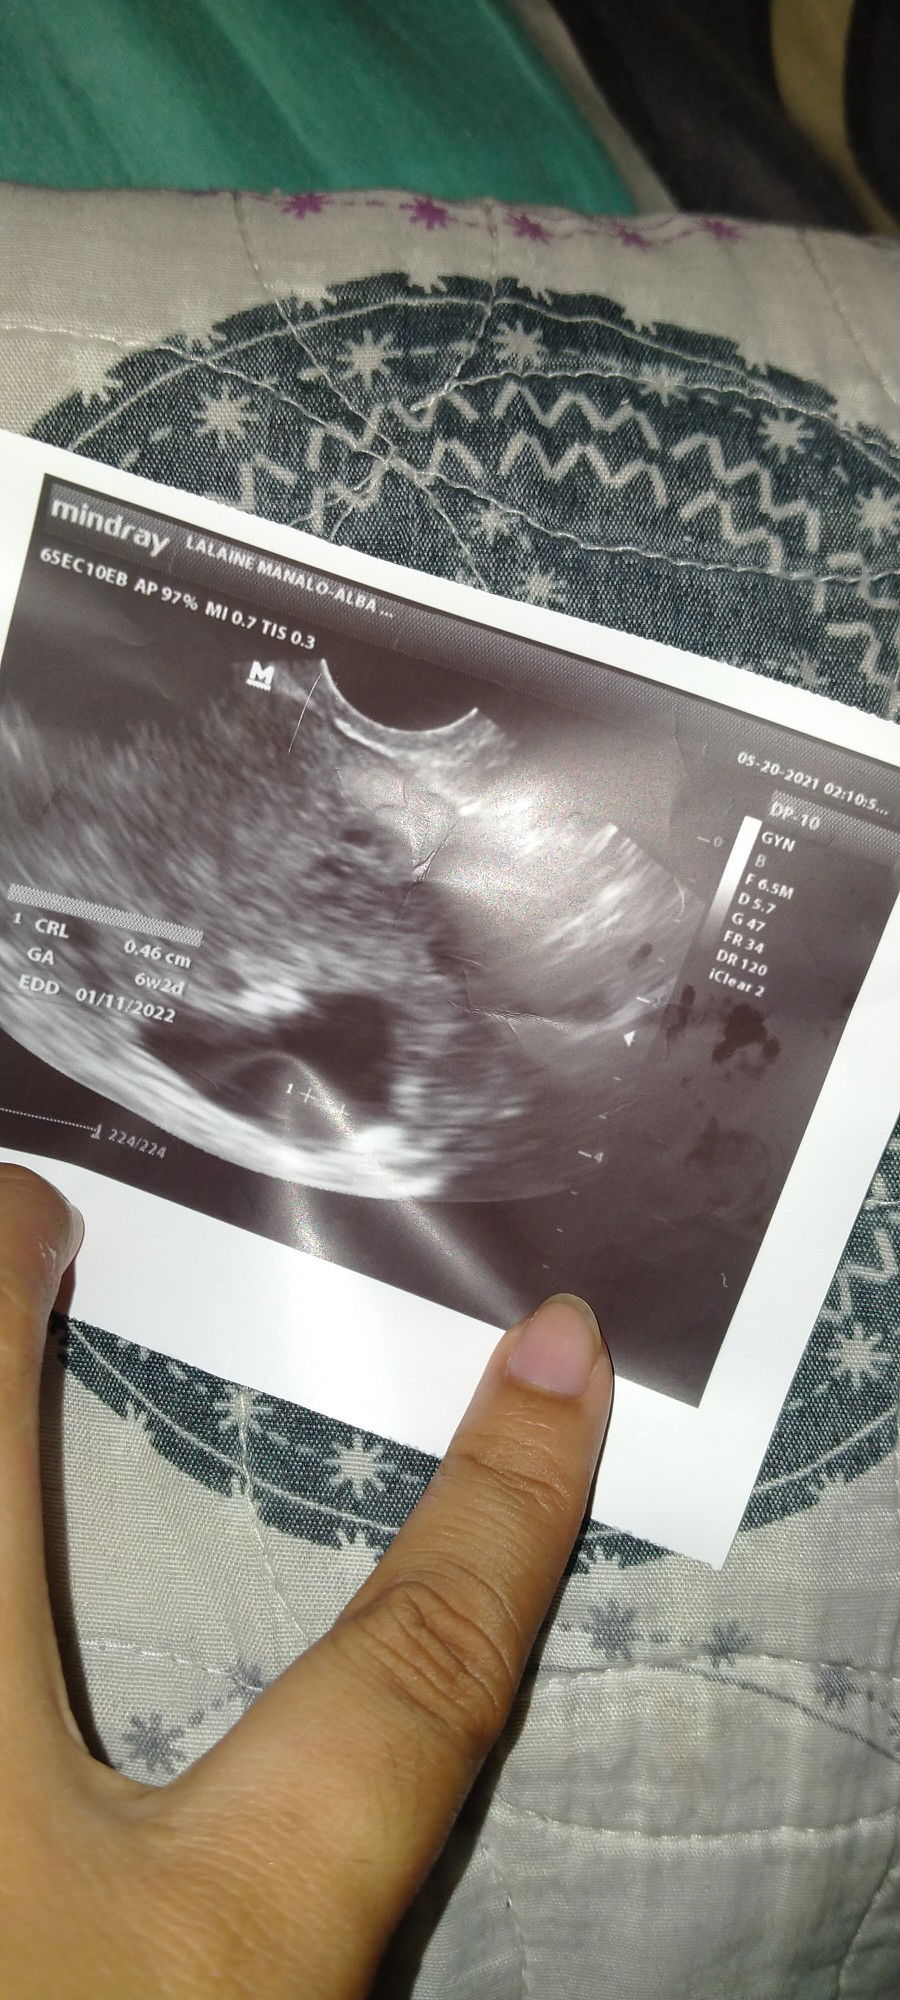

8weeks preggy wala pa din po heartbeat si baby at di nadedevelope nang ayos😞 Sabi po ni o.b anytime

pde daw po ko maagasan parang hihintayin ko na lang mawala si baby 😞 Any Suggestion po pde gawin para matuloy si baby First baby ko po sya 😭💔#1stimemom #advicepls #pleasehelp

dont give up mumsh try mo parin mag antay ng 2 weeks then magpa transv ka ulit, masyado pang maaga base sa ultrasound mo 6weeks and 2days palang, pray lang lalabas din si baby konting intay pa☺